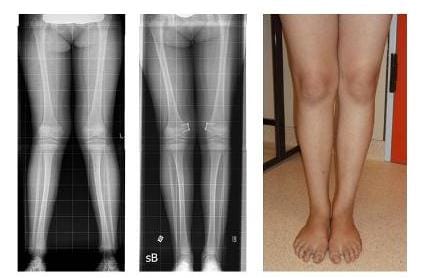

Bein-Achsfehlstellungen beim Kind und Jugendlichen

Es besteht die Möglichkeit, das Wachstum mit einer Operation zu lenken.

Hierzu überbrückt ein Implantat die Wachstumsfuge auf der Seite, wo sie zu schnell gewachsen ist. Hat sich mit dem weiteren Wachstum der nicht blockierten Seite die Beinachse begradigt, wird das Implantat wieder entfernt.

BEINACHSKORREKTUR DURCH GELENKTES WACHSTUM

Die Röntgenbilder zeigen die Korrektur der X-Beine durch Klammerung der Wachstumsfugen nach 10 Monaten

Die Röntgenbilder zeigen die Korrektur der X-Beine (linkes Bild) durch Klammerung der Wachstumsfugen (mittleres Bild) nach 10 Monaten. Klinisches Ergebnis (rechtes Bild). (Bilder: Orthopädie)